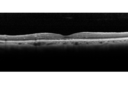

Macroaneurysm - No Leakage on FA - Fluid Absorbed - NO TREATMENT

87 year old female with decreased vision OD EXTENDED HPI: The vision in the right eye was good until a few days ago when she noticed that the vision was getting worse in the right eye. It could have been earlier and she might not have noticed it.

VA OD: sc20/100 NscJ16

VA OS: sc20/25-1 NscJ5-1

VA improved to 20/80 in 4 months and fluid absorbed without treatment

Macroaneurysm - Resolved without treatment417 views87 year old female with vision loss OD. Initial FA showed no leakage so no treatment was done and the fluid absorbed over 4 months. Initial VA 20/100, Final VA 20/80     (0 votes)